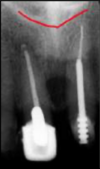

identify the anatomical structure below.

mandibular canal